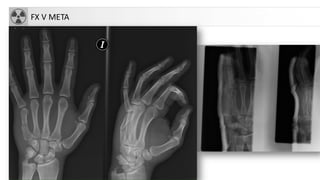

FX V META

FRACTURASMETACARPIANOS • 30-50% defracturas de la mano • Mecanismo: trauma directo • Más frecuente:FX cuello de V meta: “FX del boxeador”